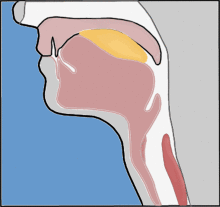

这就要从食管的解剖结构谈起。食管是食物经口进入胃肠道的长管状结构,长约25厘米。食管有三个生理性狭窄处。食管狭窄处亦是最容易发生食管异物滞留的地方。食管的第一个狭窄位于食管的起端,即咽与食管的交接处,距门齿约15cm,异物卡在此处时颈部可有明显异物感,约超过60%的食管异物发生在此处,是食管异物最容易滞留的位置;食管的第二个狭窄距门齿约25cm,由主动脉弓从其左侧穿过和左支气管从食管前方越过而形成,异物卡在此处时可有胸部异物感或疼痛感,该部位是食管内异物存留最危险的位置,尤其需要注意;食管的第三个狭窄是食管通过膈肌的裂孔处,距门齿约40cm,异物卡在此处时可有上腹部异物感或疼痛感。